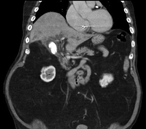

Massive retroperitoneal dedifferentiated liposarcoma in a young patient

Fernando X Moyon and others

Journal of Surgical Case Reports, Volume 2018, Issue 10, October 2018, rjy272, https://doi.org/10.1093/jscr/rjy272